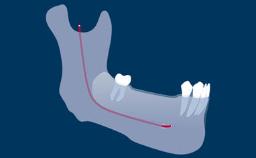

Rehabilitation of an edentulous jaw presents a number of challenges. Complete dentures have a longstanding record for rehabilitation of edentulous jaws, but they are not without functional shortcomings.

They only partially restore function, and treatment challenges increase when the residual alveolar ridges are deficient or resorbed, particularly in the mandible.

A recent systematic review has reconfirmed the recommended two-implant mandibular overdenture as the minimum standard of care in complete denture therapy.